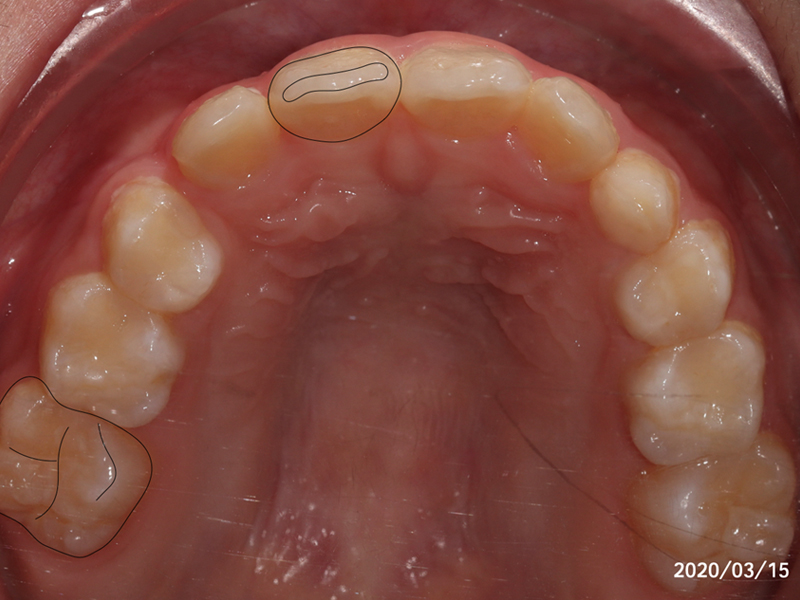

來看看Kevin 的矯正案例,8歲,牙弓發育不足。

Kevin 還在混合齒列的時期,也就是乳牙的替換期。第一次媽媽帶 Kevin 來門診時,跟我們分享了 Kevin 口呼吸的情況,鼻子常常容易鼻塞、過敏。這也導致了 Kevin 的舌頭時常放在口底,無法有效地引導顎骨生長,產生了惡性循環。

我們利用兒童隱適美幫 Kevin 擴弓

左圖是進行兒童隱適美的療程一年後,我們看到 Kevin 的變化。

黑色標示處是兩顆恆牙,分別是右側正中門牙,與右上第一大臼齒。按照 Kevin 的生長來看,如果在完全未介入的情況下,原先三顆乳牙的地方,要排入四顆恆牙,會有嚴重的空間不足。因此可以預期 Kevin 的犬齒會從上方牙齦中冒出來。(也就是俗稱的高位虎牙)

令人欣喜的是:我們幫Kevin的牙弓擴開至少了1.5顆恆牙的寬度,讓Kevin的所有恆牙都有足夠的空間都能朝理想的位置生長。